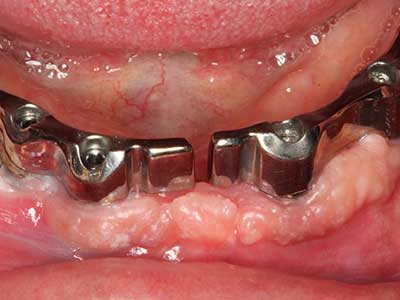

Пиезохирургията има допълнителни предимства при събиране на костни блокове. В допълнение към високата прецизност при остеотомията, описана по-горе, употребата на фините режещи накрайници значително намаляват загубата на материал. Голяма загуба на материал по време на събиране може да се очаква с дебелите накрайници, особено при употреба на борери Линдеман (Lakshmiganthan, Gokulanathan et al. 2012). Базалното разделяне, което е необходимо, особено за присадка на блок при ретромолар, е улеснено от специално създадени правоъгълни триони. В резултат на това, пиезохирургията е разглеждана като прецизна, улеснена и безопасна процедура за събиране на костни блокове в ретромоларното пространство (Happe 2007) (Фиг. 1-12).